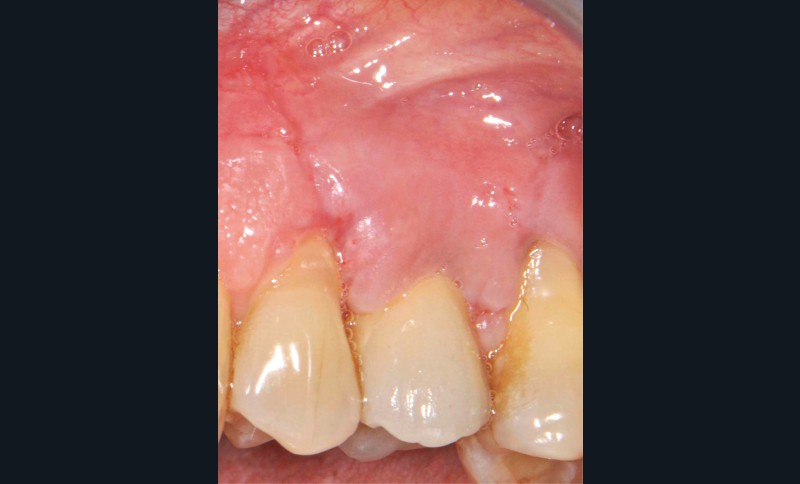

13 et 14. À 3 ans, une régénération osseuse satisfaisante et un bel aspect des tissus péri-implantaires sont observés. Les poches font 3 mm en mésial, distal et palatin, et 2 mm en vestibulaire. Il n’y a pas de saignement au sondage.